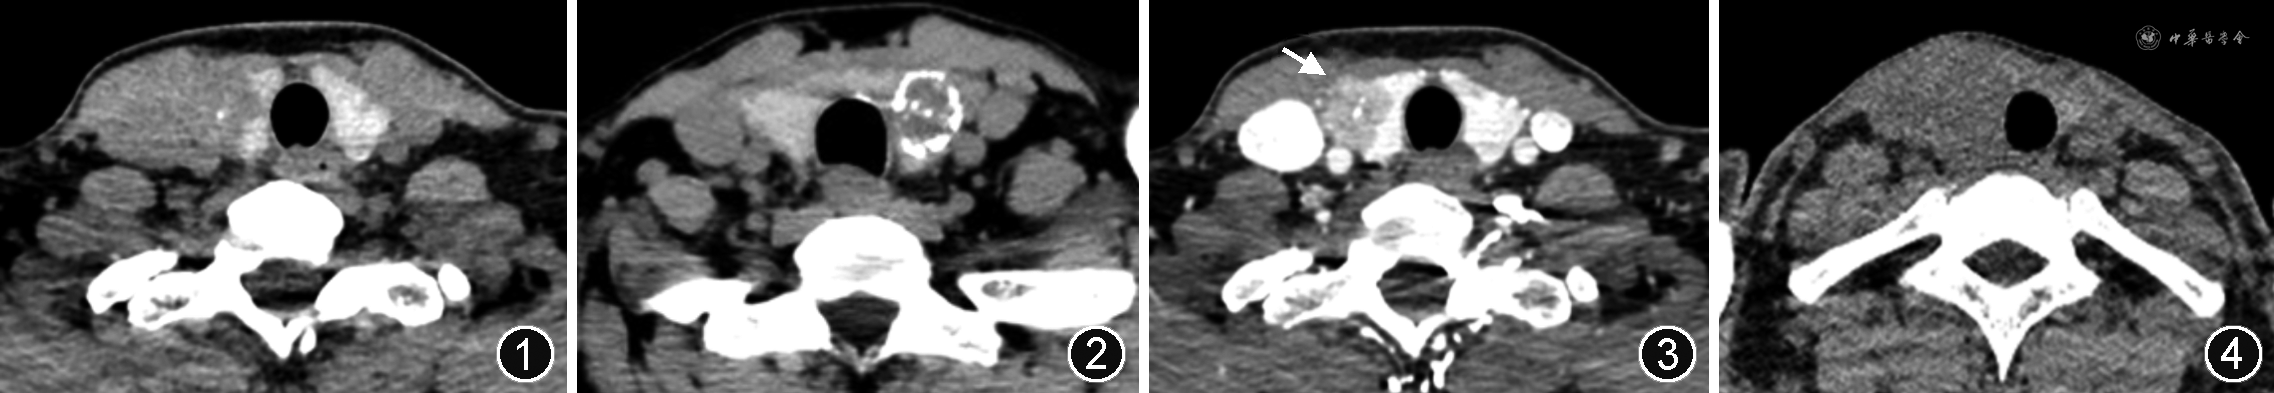

形态不规则、微钙化、增强后边界模糊或缩小、“咬饼征”是诊断甲状腺乳头状癌的主要CT征象[6,10, 11]。(1)钙化。微钙化是指最大径≤2 mm的钙化(图1),随着微钙化数量的增加,尤其是分布集中的簇状微钙化,甲状腺癌的可能性明显升高,而弥漫性微钙化几乎均为甲状腺乳头状癌[12, 13]。对于环状钙化,钙化环中断被认为是甲状腺恶性结节的重要依据(图2),完整的钙化环多见于甲状腺良性结节,这是由于恶性结节常呈侵袭性生长,会破坏钙化边界,导致钙化环的连续性中断[14]。(2)增强后瘤体边界模糊或缩小。是指增强后甲状腺组织与瘤体间的密度差异小于平扫时两者间的密度差异,造成增强后结节边缘更模糊、范围缩小。此征象诊断乳头状癌的灵敏度和特异度均可达80%以上[6]。(3)“咬饼征”。又称“甲状腺边缘中断征”,泛指瘤体边缘与甲状腺边缘具有一定的接触面,接触面较平直,并非杯口状表现,其病理基础为瘤体接近或累及甲状腺被膜(图3)。此征象诊断甲状腺乳头状癌的特异度可达94%,灵敏度74%[6]。

2.甲状腺滤泡状癌:以滤泡状结构和血管或包膜侵犯为主要组织学特征的分化型甲状腺癌,是甲状腺第2常见恶性肿瘤,约占甲状腺癌的10%。本病多见于碘缺乏地区,因此其发病可能与碘营养状态有关[15]。甲状腺滤泡状癌多为形态规则的圆形或椭圆形,这点与乳头状癌有很大不同,且其包膜较厚,CT平扫不能很好地分辨包膜,增强CT对瘤周的低强化或无强化包膜显示更清晰。结节性甲状腺肿伴腺瘤样增生和滤泡状腺瘤也具有包膜,病灶表现为包膜不完整时更支持滤泡状癌的诊断[4,16]。滤泡状癌CT密度可均匀或不均匀(图4),增强后一般呈低强化或等强化,瘤体内部出现低强化或无强化的星芒状瘢痕或坏死是较为特征性的表现,坏死明显者呈厚壁囊肿状,壁厚薄不均。